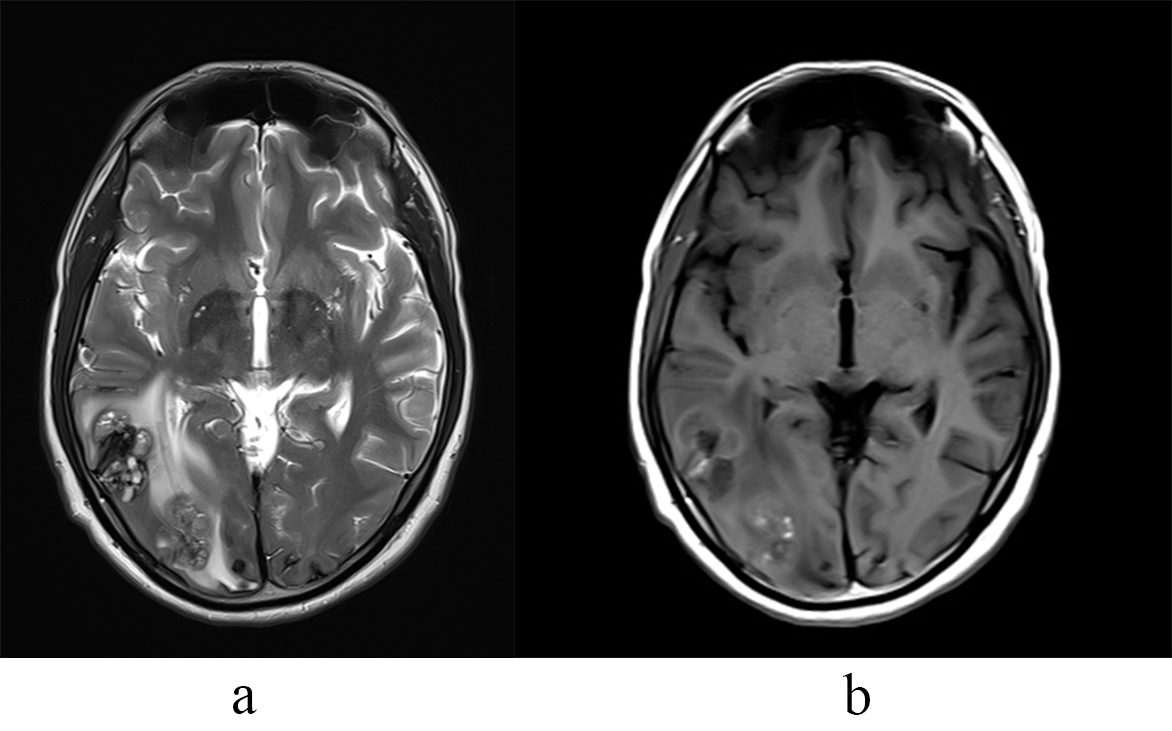

We encountered a 42-year-old male, with a history of total excision of a left atrial myxoma in April 2023, presented in September 2024 with mild weakness, tingling, and numbness in the left upper and lower limbs for two months. He also experienced persistent headaches and had two episodes of generalized tonic-clonic seizures. An echocardiogram confirmed no recurrence of the atrial myxoma. Brain magnetic resonance imaging (MRI) revealed T2/fluid attenuated inversion recovery sequences (FLAIR) heterogeneous mixed-signal intensity lesions in the bilateral parietal, right temporal-occipital, and right frontal regions, accompanied by surrounding edema and heterogeneous post-contrast enhancement, suggestive of parenchymal metastasis (Fig. 1). Digital subtraction angiography (DSA) of the brain demonstrated multiple fusiform aneurysms in the cortical branches of the bilateral anterior cerebral artery (ACA), middle cerebral artery (MCA), and posterior cerebral artery (PCA) (Fig. 2). The treatment options were discussed with him, and he opted to undergo chemotherapy and radiotherapy.

Fig. 1. Right temporo-occipital lesions on MRI. (a) T2W MRI shows right temporo-occipital lesions with heterogeneous signal and edema. (b) T1 Post contrast shows mild heterogeneous enhancement. T2W MRI, T2 weighted magnetic resonance imaging.